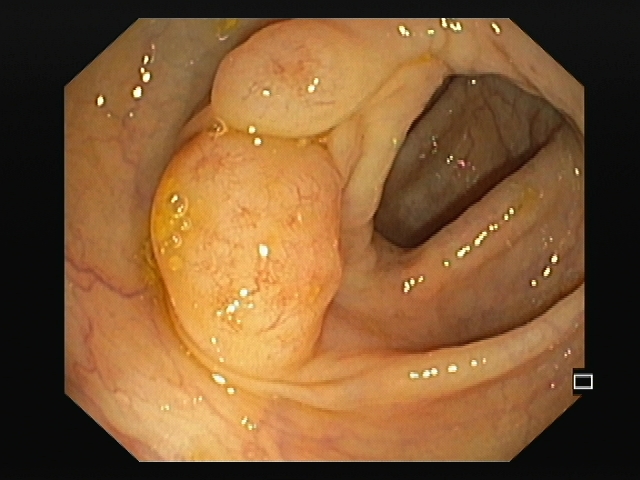

A messy web

1º Prémio - Fotografia